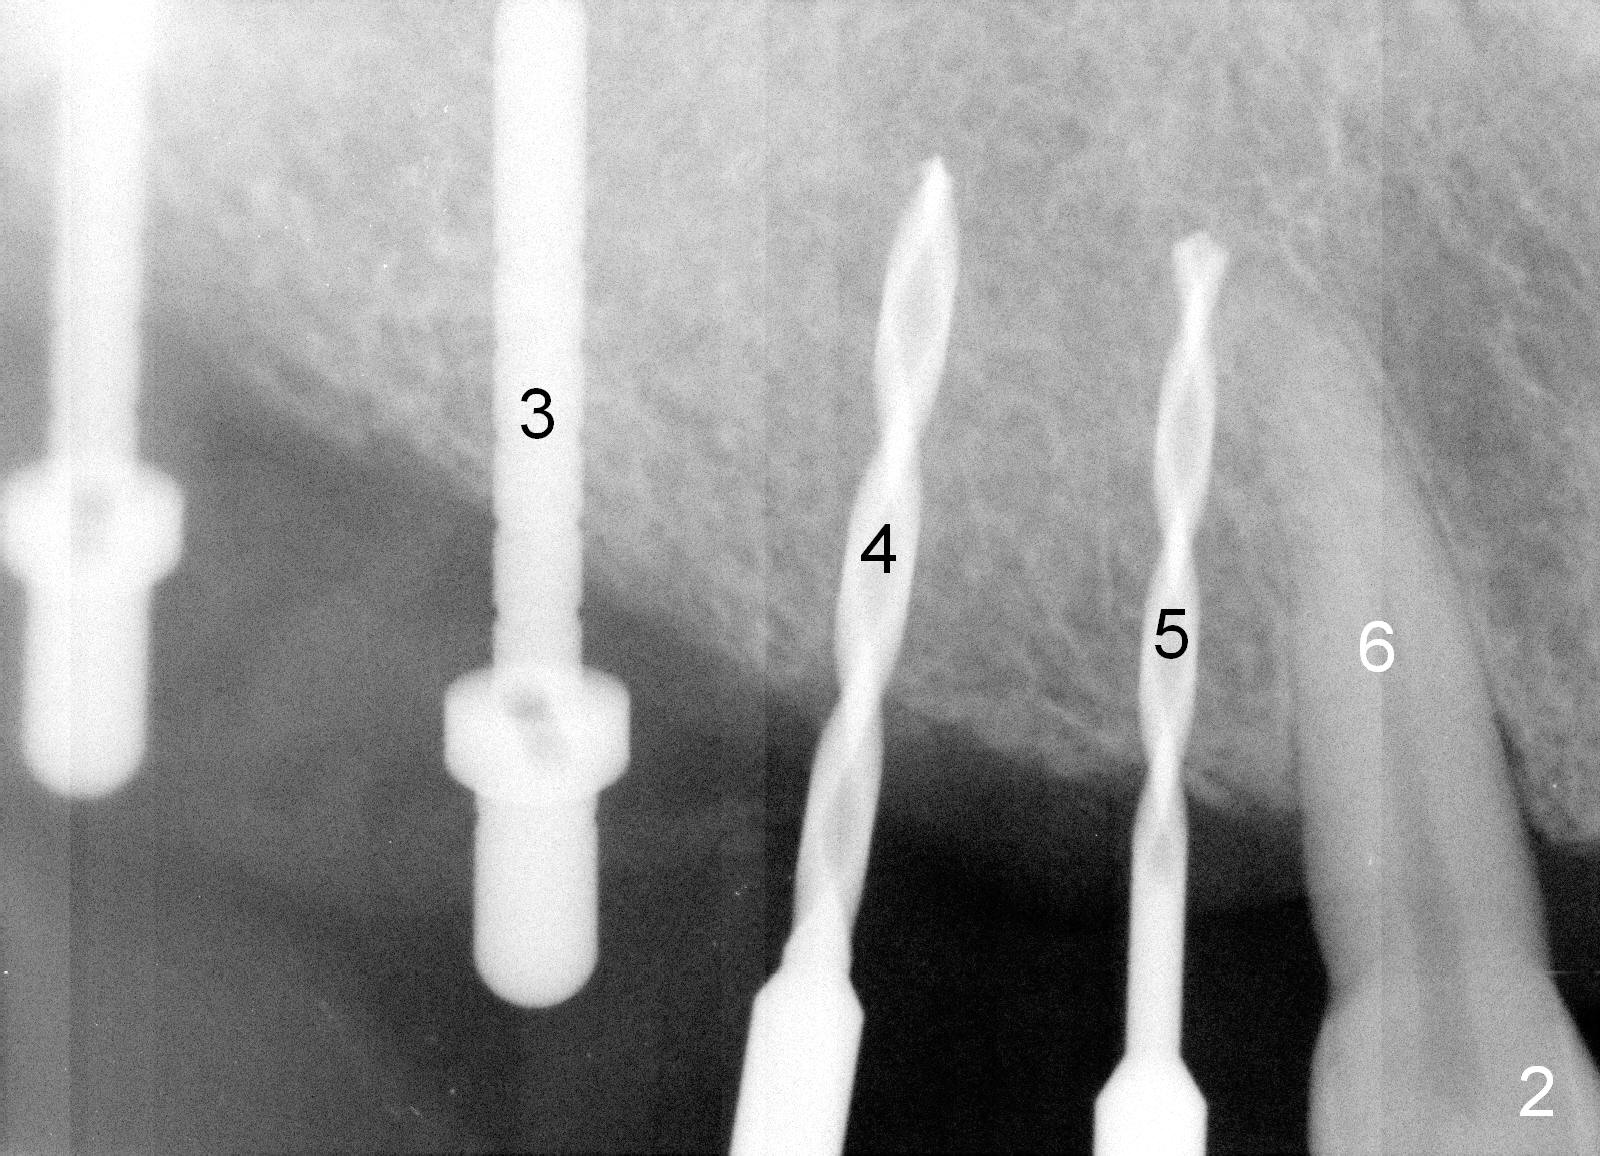

Osteotomy in the upper posteriors starts through a surgical stent for 12 mm. After incision, each osteotomy is examined, adjusted and extended 2 mm shy of intended (Fig.1,2). It appears that the trajectories at #4,5 are off (Fig.2). After re-adjustment, the trajectories are acceptable (Fig.3 (red dashed line; part of the root of the tooth #6)). Four implants are placed basically in accordance with the plan: 5.9x10 mm at #2, 5x14 at 3, and 3x14 mm 1-piece at 4 and 5 (Fig.4,5). Fig.6 shows the narrow ridge at #4 and 5 after implant placement. Although abutments are placed at #2 and 3, an immediate provisional bridge cannot be fabricated because of lack of enough clearance (supraeruption of the opposing dentition).